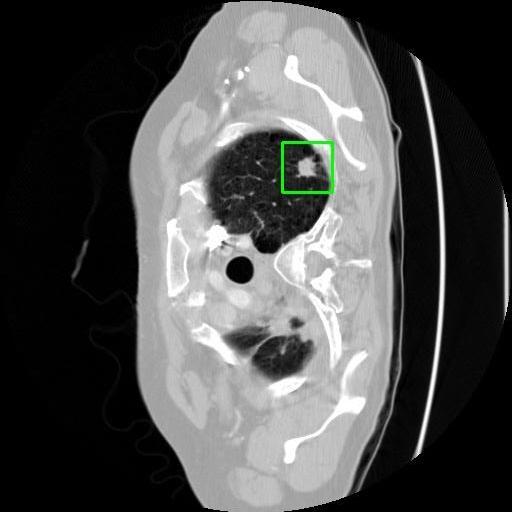

We developed an AI-based system using deep learning models for analyzing lung CT scans to detect and classify pulmonary nodules. We chose the YOLOv11 architecture for its enhanced object detection capability and adapted it specifically for medical imaging, incorporating pixel-level precision and severity classification.

Classification into three severity levels with colored bounding boxes.

Successfully built and deployed an AI model (YOLOv11) capable of detecting lung nodules in CT scans with high accuracy and real-time performance.

Designed a severity classification system that categorizes nodules into null, moderate, and severe using colored bounding boxes, assisting in rapid clinical decision-making.